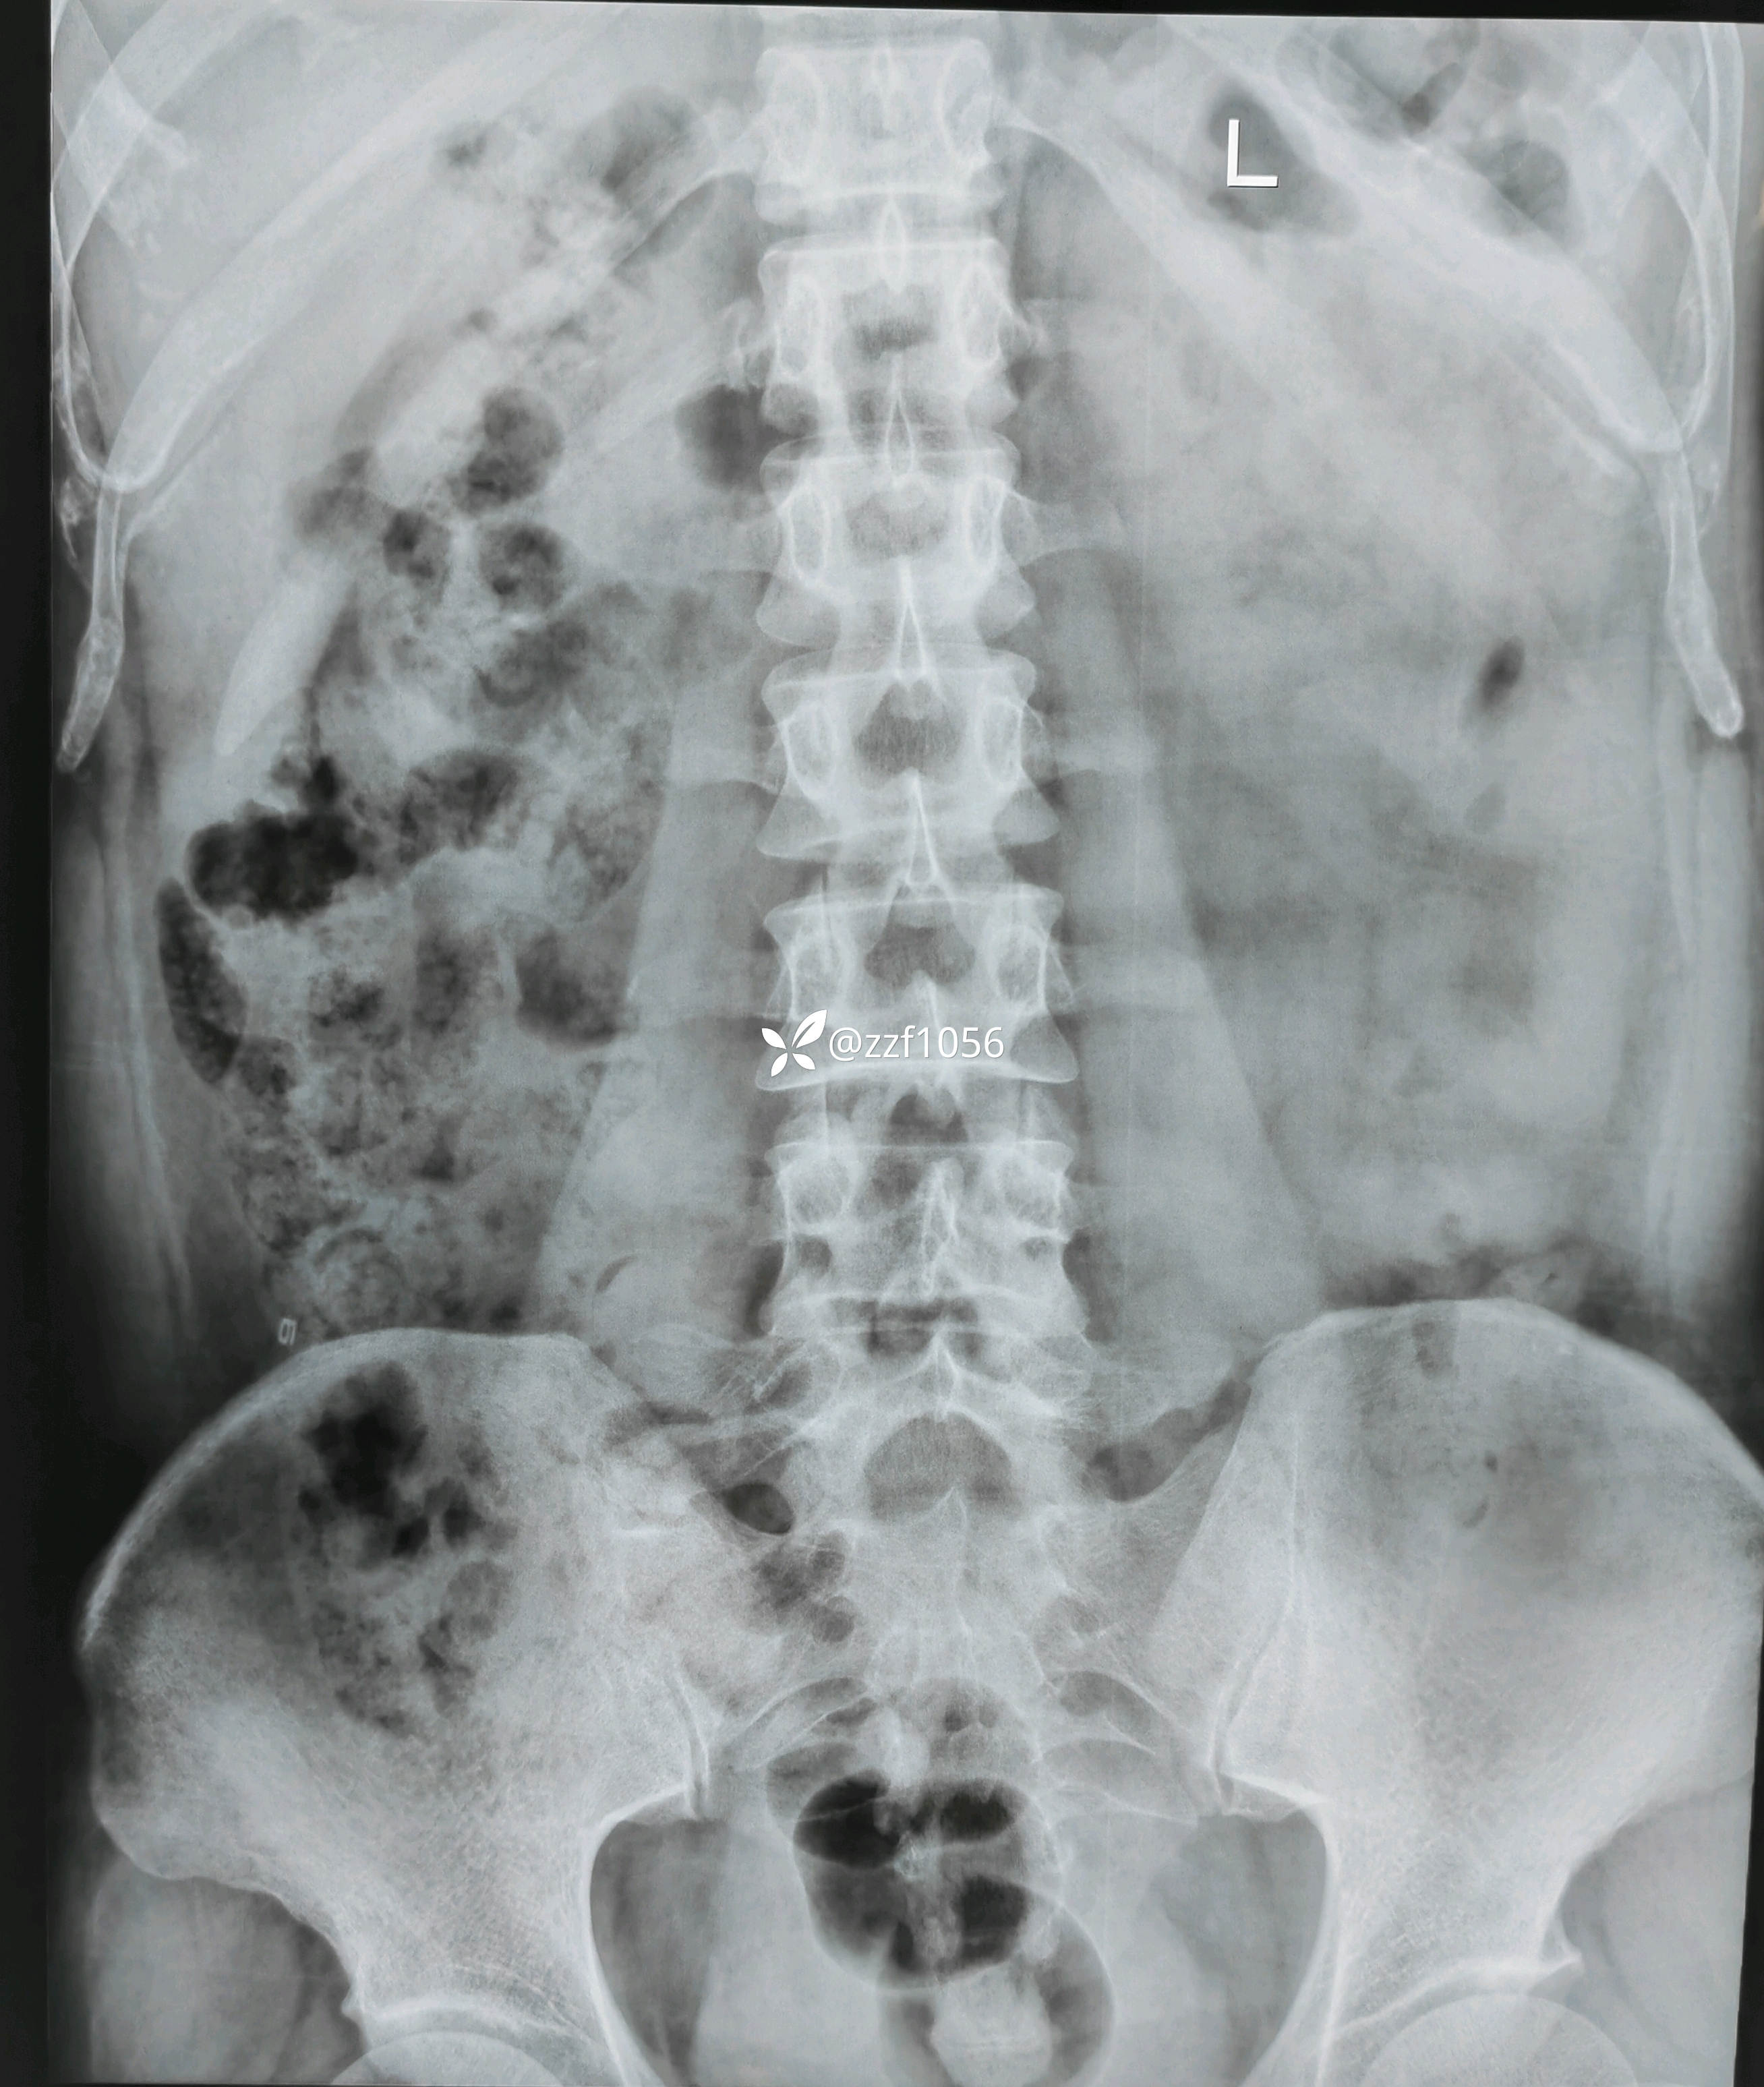

患者男性,39岁,腰痛伴右下肢疼痛麻木不适4个月,加重半个月。

4个月前右膝前叉韧带断裂在我院行重建术,当时腰椎间盘突出症状较轻,一直行保守治疗,半月前LDH症状加重,当地输液半个月无好转,只能被迫俯卧体位,严重影响生活劳作。查体典型右侧L5根性症状,患者同意微创手术,后路ube还是侧路椎间孔镜?

入院诊断:腰椎间盘突出症伴神经根病(L4/5)